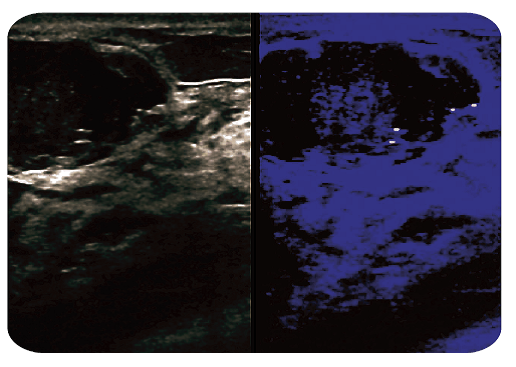

Tryb obrazowania Dual: Prawo/Lewo oraz Góra/Dół pozwalający lepiej porównywać te same obszary lub widzieć je w różnych trybach pracy (np. B/CD, B/Elasto, B/SMI).

Innowacyjna technika obrazowania pozwalająca na wizualizację mikroskopijnych przepływów z filtracją artefaktów ruchowych dostępna zarówno w trybie kolorowym jak i monochromatycznym.

Zapewnia wizualizację przepływów o niskich prędkościach, bardzo wysoką rozdzielczość i prędkość odświeżania, co pozwala ocenić niezwykle niskie przepływy np. w korze nerek, węzłach chłonnych, guzach, w przypadku neowaskularyzacji np. blaszek miażdżycowych w naczyniach, czy uszkodzeń ścięgien (tendinopathy) i niedokrwieniu.

Umożliwia również obrazowanie przepływów w komorach serca płodu w 10-12 tygodniu, co pozwala na bardzo wczesną diagnostykę wad.

Zapewnia też bardzo dokładną wizualizację drobnych naczyń np. unaczynienie nerek bez potrzeby podawania kontrastu, umożliwia również diagnostykę w przypadku refluksu, obserwację drobnych naczyń w przypadku oceny skrętu jąder u dzieci i w wielu innych przypadkach.